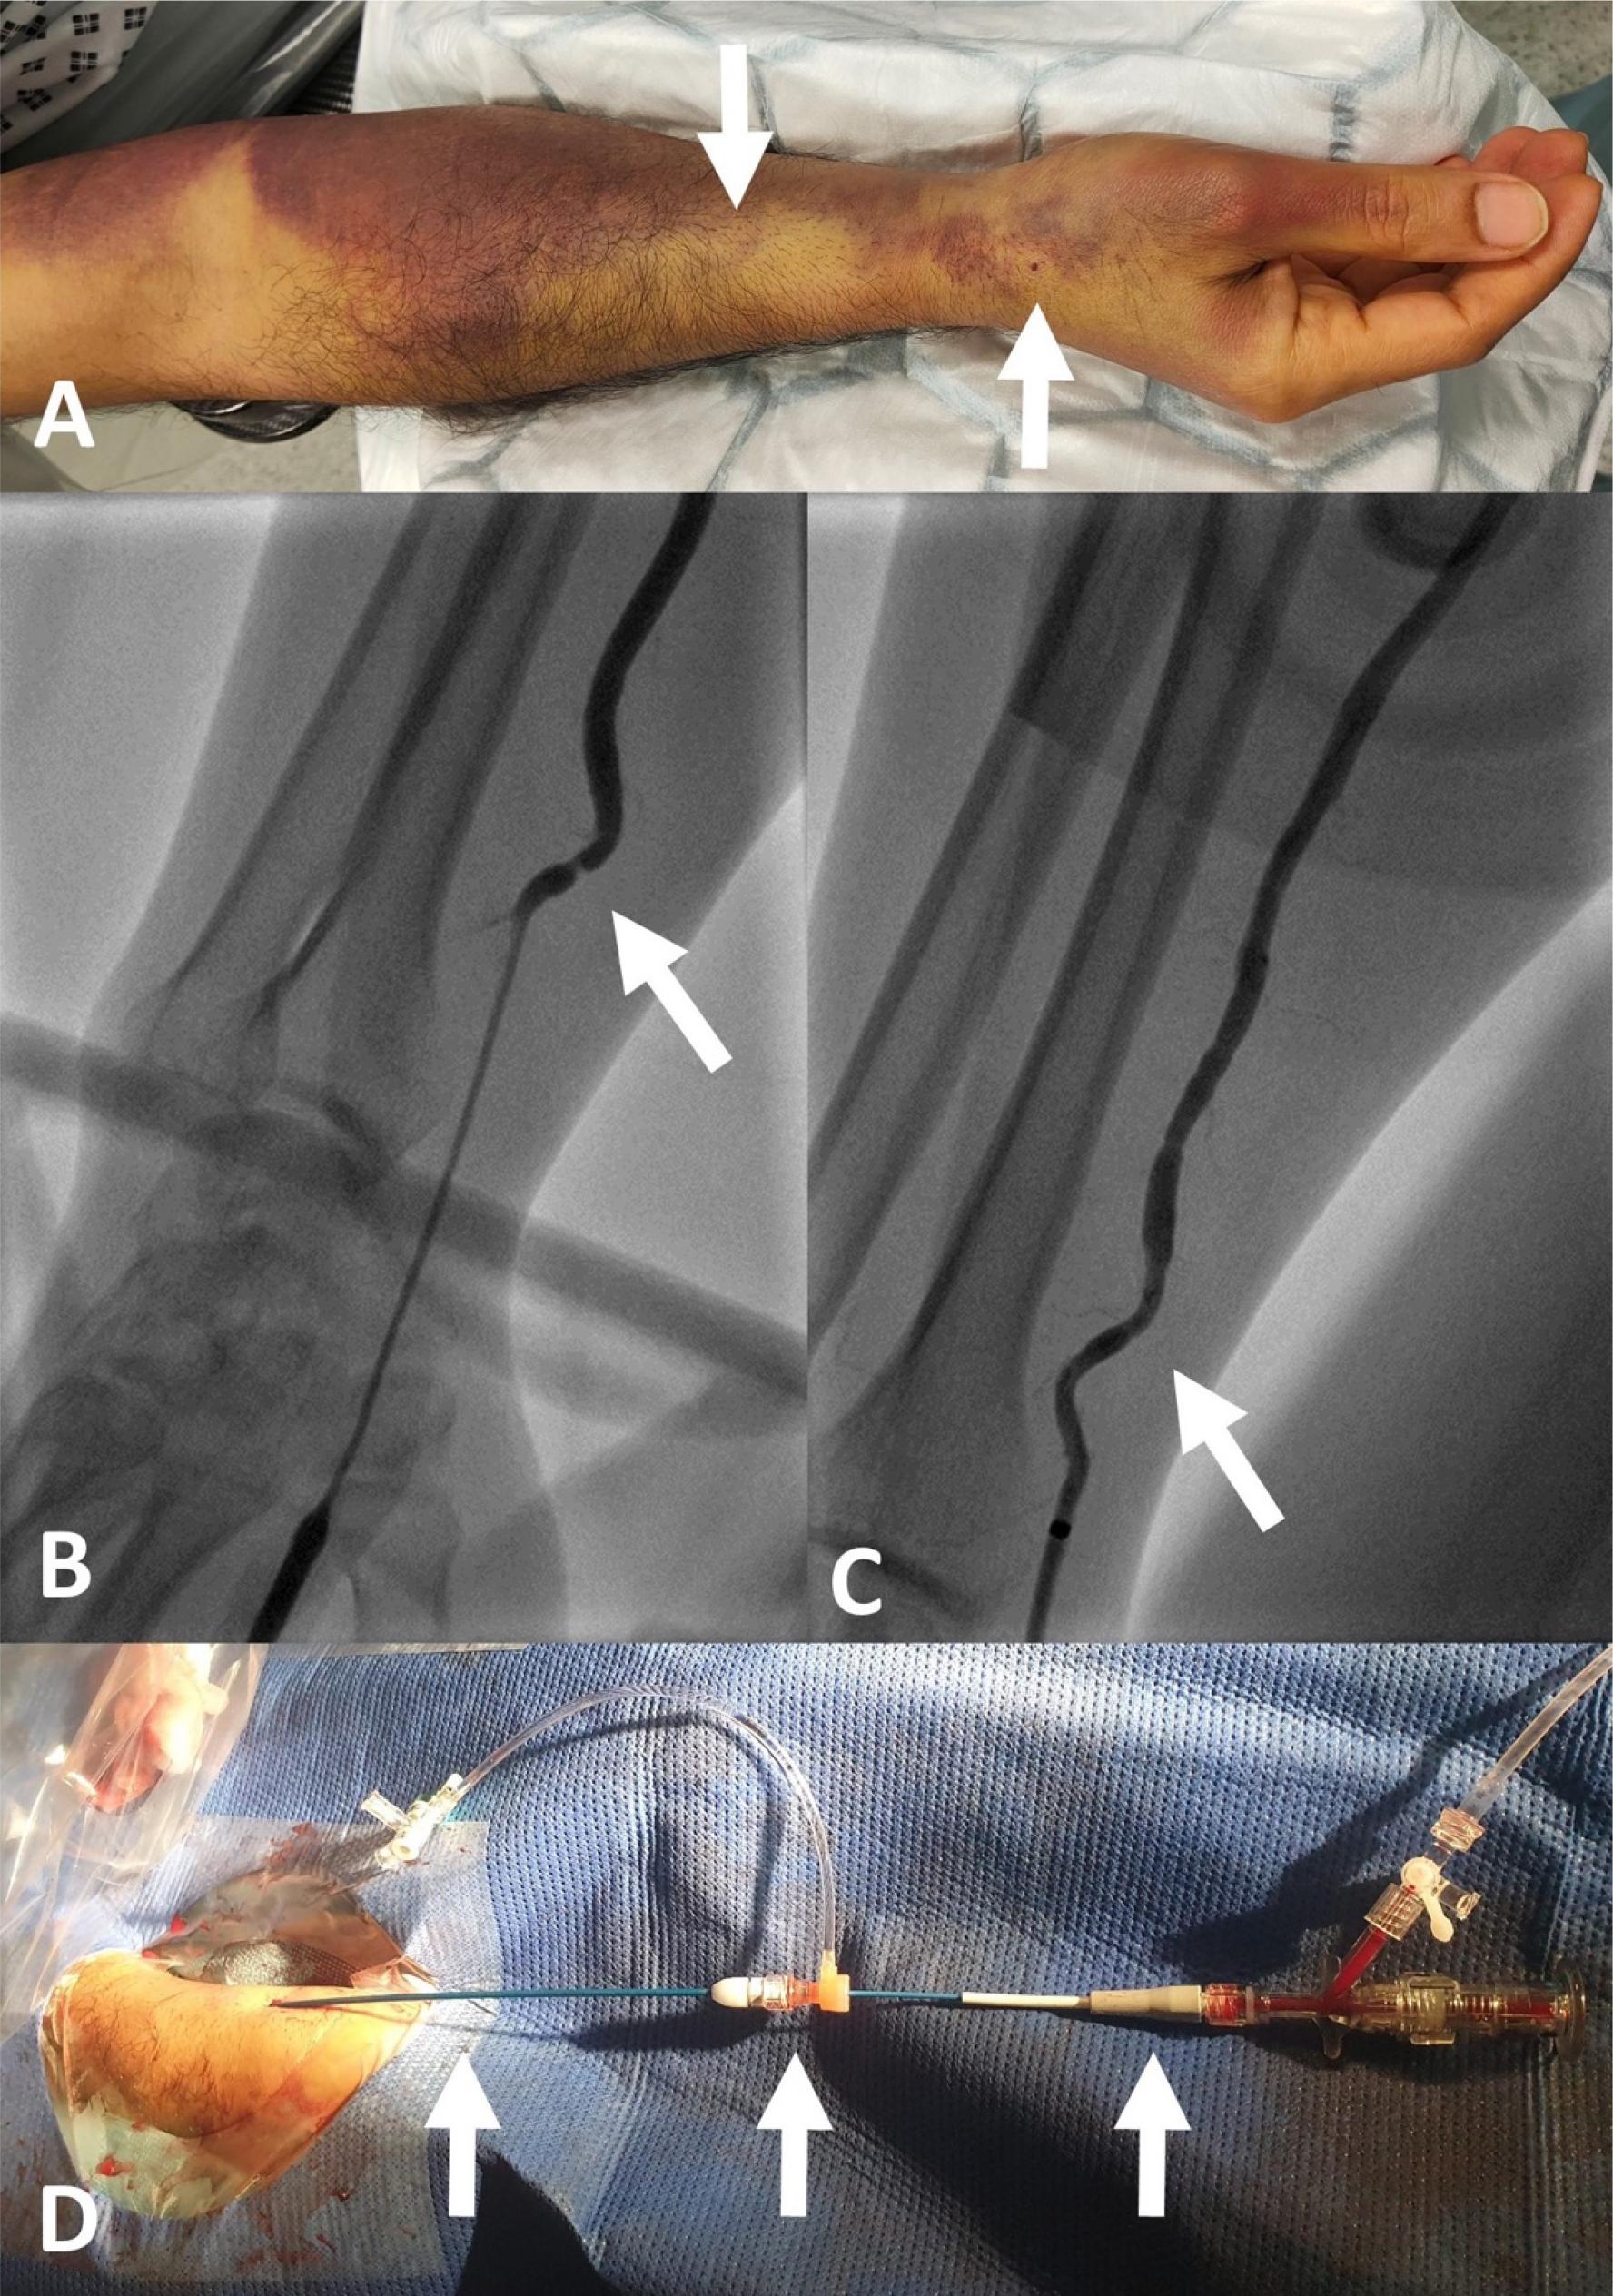

A – Forearm hematoma at day five with extensive bruising, right arrow indicates the prior dRA puncture site, and the left arrow points to likely site of perforation. B – Radial angiogram with arrow pointing to a napkin ring lesion corresponding to the tip of the prior 6Fr sheath. C – Repeat radial angiogram following staged coronary intervention showing no new disruption. D – The extra-long radial guiding sheath, left arrow points to the 90cm 5Fr hydrophilic coated guiding sheath (Cook Medical, Bloomington, IN, USA), middle arrow points to the short haemostatic valve (Terumo Corporation, Tokyo, Japan) and the right arrow points to the 5Fr EBU3.5 guiding catheter.

When the patient was transferred to the ward, his right forearm was noted to be tense. Tirofiban was discontinued, and additional pressure dressing was applied around the forearm. Interestingly, the dRA access site remained flat, and there was no extension of swelling into the hand, which would always be the case if the bleeding was from the dRA puncture site. Fortunately, compartmental syndrome did not ensue. He had staged coronary intervention to the left circumflex artery five days later. Extensive bruising around the forearm spread above the elbow, hence grade 4/5 on the EASY Hematoma Scale (Figure 1A) [6]. The right dRA was re-accessed with a 7cm 4Fr Micropuncture Pedal Access sheath (Cook Medical, Bloomington, IN, USA) [5]. A radial arteriogram was performed following 200ug of nitroglycerine given intra-arterially, and this showed a “napkin ring” lesion corresponding to the shape of the tip of the previous 6Fr sheath (Figure 1B). A guidewire was advanced down the artery, and an 11cm 4Fr Prelude IDeal sheath (Merit Medical, Utah, USA) was swapped in, followed by a 4Fr JR4 diagnostic catheter that was used to intubate the right coronary artery, revealing a patent artery. Next, a “long” 260cm J-tipped 0.035” exchange length wire was advanced into the aortic root, and the sheath was removed. A 90cm 5Fr hydrophilic coated guiding sheath (Cook Medical, Bloomington, IN, USA) was then introduced into the ascending aorta, and a short hemostatic valve (Terumo Corporation, Tokyo, Japan) was attached to the other end of the catheter forming an extra-long radial sheath. This allowed a 5Fr EBU3.5 guiding catheter to be easily advanced down the ascending aorta, and the left coronary artery was engaged. Coronary intervention to the circumflex artery was completed uneventfully. Before the guiding sheath was removed, a repeat radial arteriogram was performed, showing no contrast extravasation to suggest rebleeding (Figure 1C). Figure 1D shows the set-up of the radial sheath used in this case.